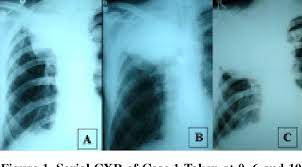

Lung cancer is often divided into two types: Lung cancer is the leading cause of cancer death worldwide, with approx. Tuberculosis (tb) is caused by bacteria (mycobacterium tuberculosis) that most often affect the lungs. Tuberculosis (tb) is a contagious infection that usually attacks your lungs. Lung cancer is most often discovered by mistake if it is detected in the early stages.

Since mycobacterium tuberculosis (mtb) is an intracellular organism, bacterial dna could integrate to bronchial epithelial cells inducing neoplastic transformation. 90% of cases being attributable to smoking. Lung cancers are generally divided into 2 main categories: Is it possible for the doctor to mistake a possible lung cancer for tb? Can lung cancer be found early? Even when lung cancer does cause symptoms, many people may mistake them for other problems, such as an. When lung cancer is suspected, a physician will perform a thorough history and physical exam. The occurrence of pulmonary tuberculosis (ptb) and lung cancer as comorbidities has been extensively discussed in many studies. The incidence of both conditions remains high in many developing countries, especially in east asia. In the past, it was well known that lung cancer is a specific epidemiological successor of ptb and that lung cancer often develops in scars caused by ptb. Living with advanced breast cancer. Pulmonary tuberculosis and lung cancer. Lung cancer is most often discovered by mistake if it is detected in the early stages.

Care guide for lung cancer. Lung cancer is the leading cause of cancer death worldwide, with approx. Possible causes, signs and symptoms, standard treatment options and means of care and support. Patients with lung cancer are often misdiagnosed as pulmonary tuberculosis leading to delay in the correct diagnosis as well as exposure to inappropriate. 7 incidence the incidence of lung cancer in tuberculosis patients was about 2%.